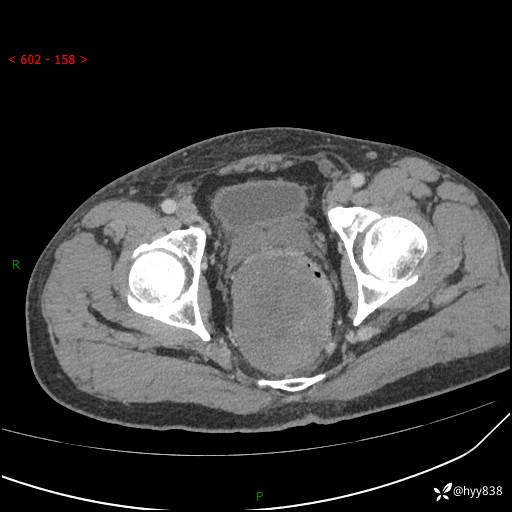

盆腔CT平扫+增强